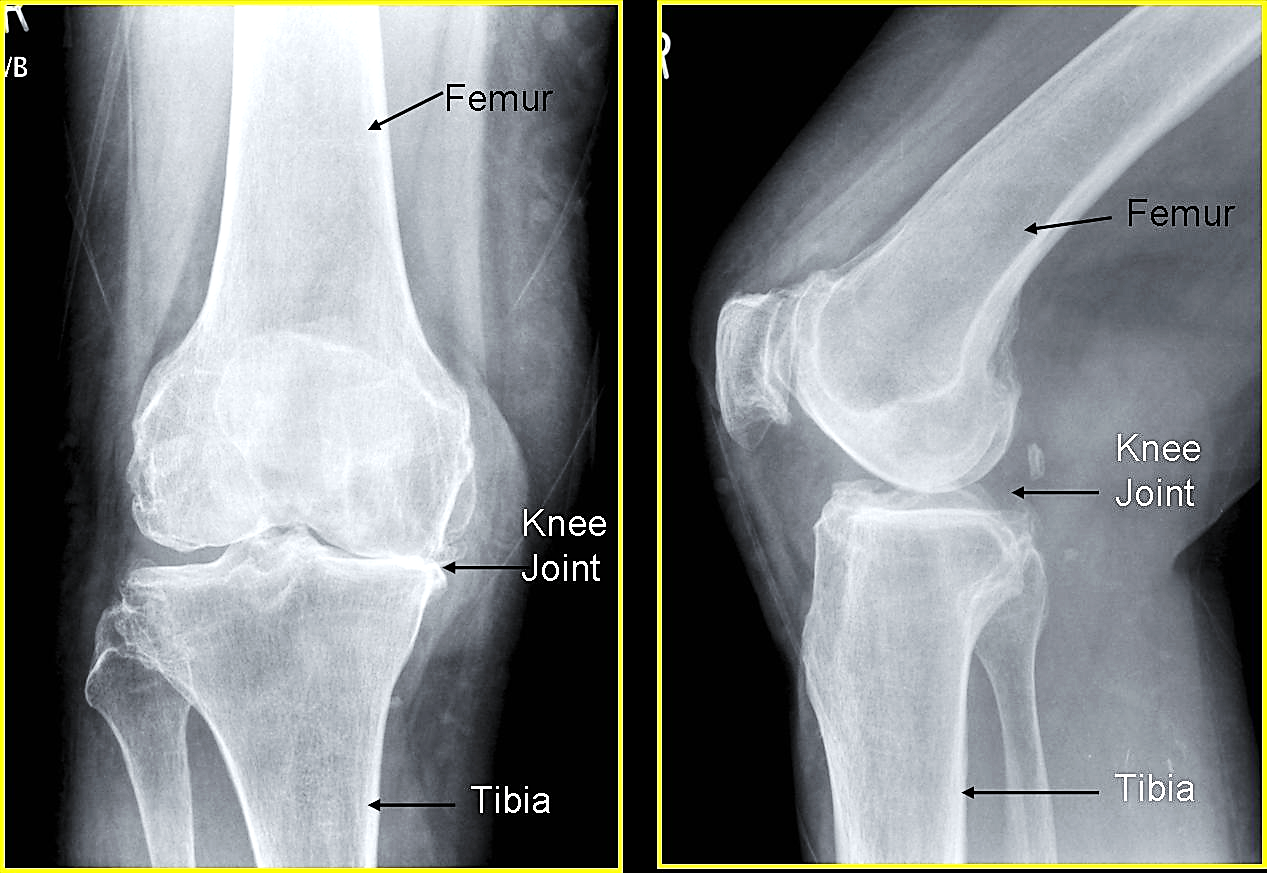

PEMERIKSAAN X-RAY LUTUT - PORTAL MyHEALTH

PEMERIKSAAN X-RAY LUTUT - PORTAL MyHEALTH